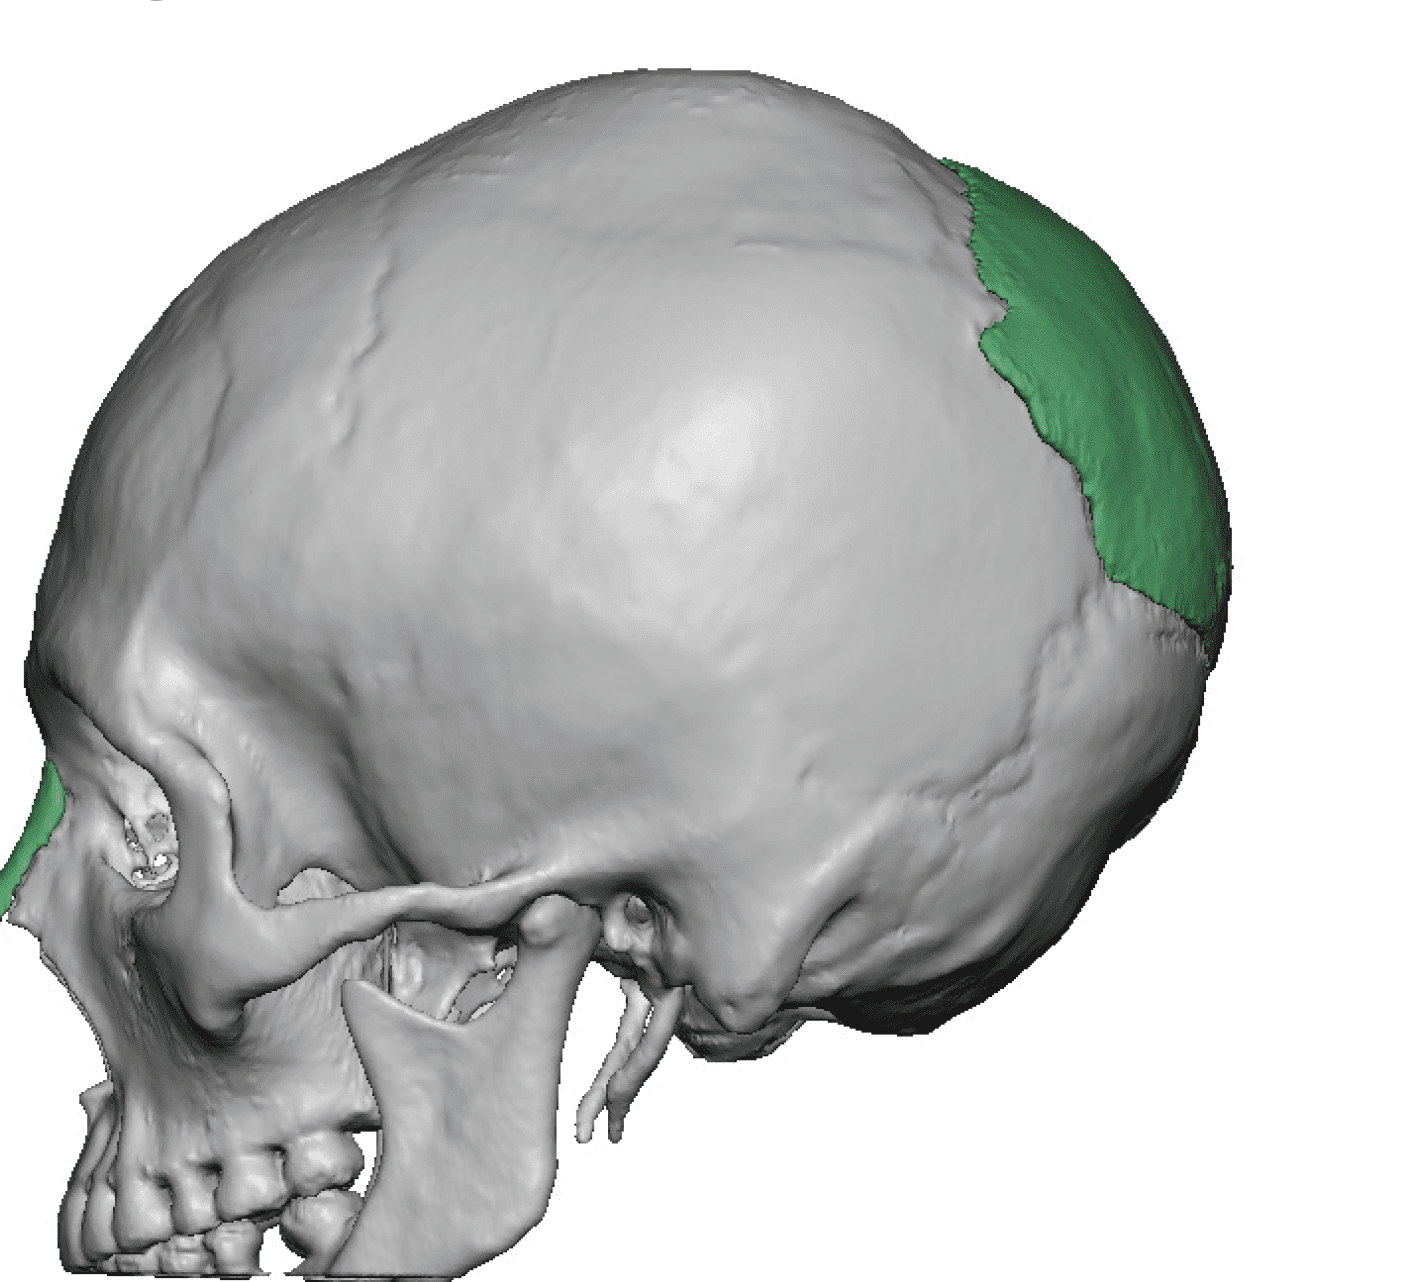

Patient 84

Desire for change of head shape from front view form an inverted V shape to a rounder and wider head shape.

Placement of custom extended forehead-temporal implants through incisions in the crease behind the ear. (he had a prior back of head skull implant which is green in the implant designs and which the head widening implants partially covered it)

Desire for change of head shape from front view form an inverted V shape to a rounder and wider head shape.

Placement of custom extended forehead-temporal implants through incisions in the crease behind the ear. (he had a prior back of head skull implant which is green in the implant designs and which the head widening implants partially covered it)